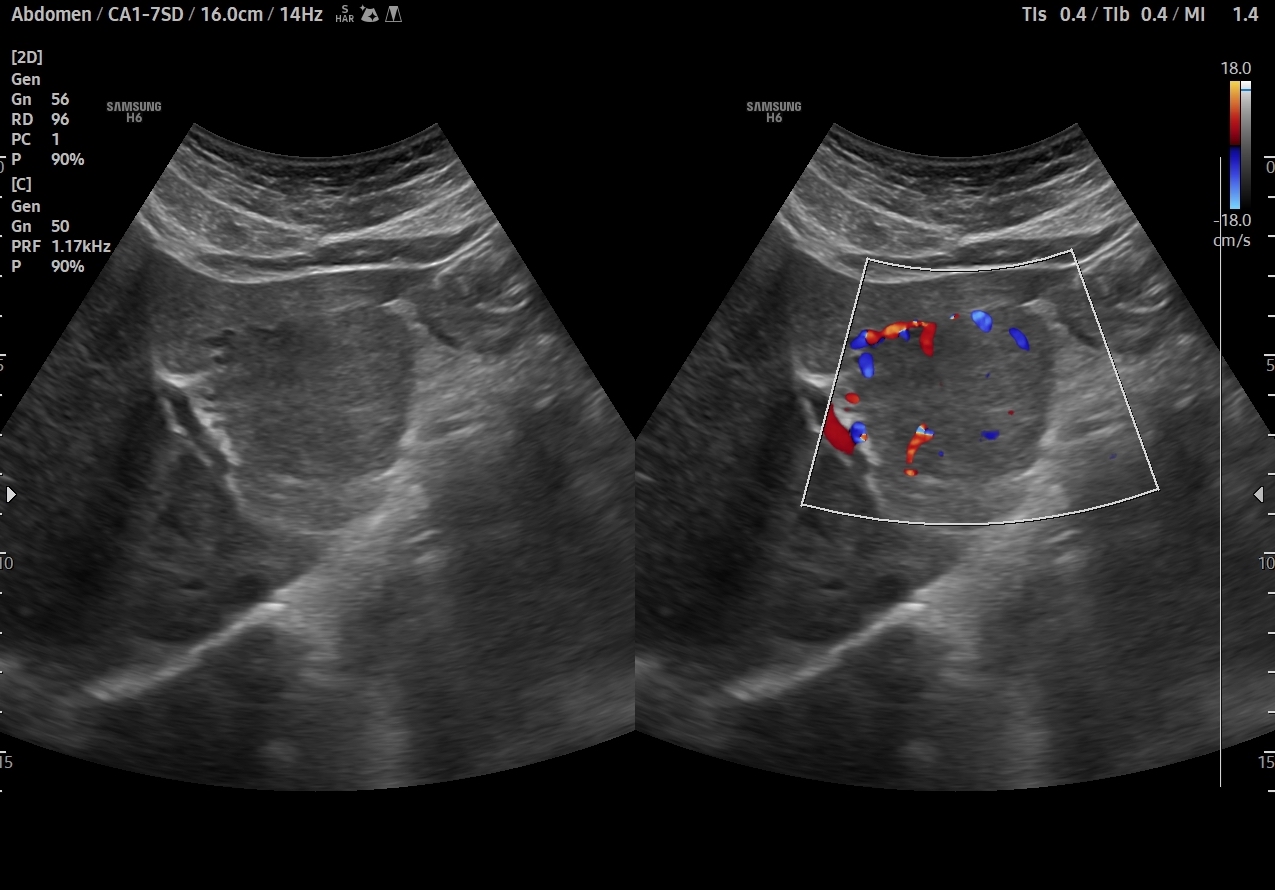

En el lóbulo hepático izquierdo visualizamos lesión focal iso-hipoecogénica respecto al parénquima hepático circundante que mide 4,6 x 4,5 x 3,9 cm y que presenta un aumento de la señal Doppler. Vemos la imagen tanto en cortes transversales como en cortes longitudinales, también con el modo Doppler activo. Resto de parénquima hepático y vía biliar de aspecto normal, sin otras alteraciones.